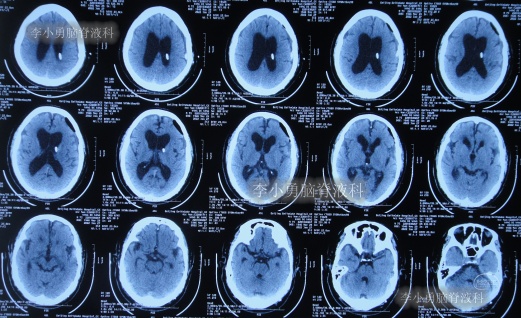

出院后再次转住入当地的第1家医院进行康复治疗,在该院康复治疗半年多的时间,不但没有持续好转,反而再次腰疼,走路不稳,且还出现了尿失禁的持续加重症状;治疗期间曾6次查头部影像(图-13、图-14、图-15、图-16、图-17)均示脑积水不断加重的趋势。

图-13:2021年5月22日头部核磁

图-14:2021年6月2日头部核磁

图-15:2021年7月24日头部核磁

图-16:2021年8月28日头部核磁

图-17:2021年9月28日头部CT